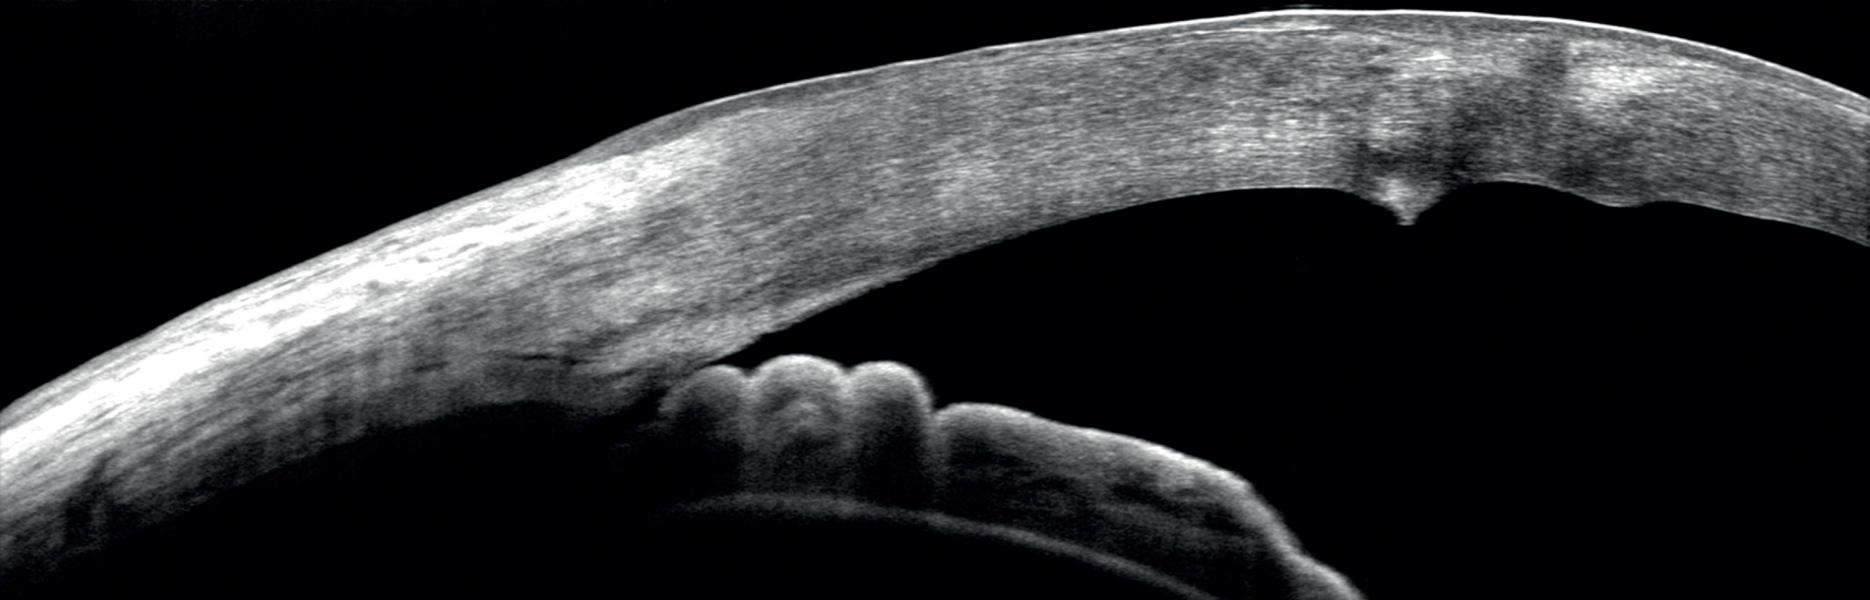

Η Οπτική Τομογραφία – ΟCT είναι μία μη επεμβατική μέθοδος τομογραφικής απεικόνισης της δομής του αμφιβληστροειδούς και του προσθίου ημιμορίου του ματιού. Η απεικόνιση είναι ανάλογη αυτής της βιοψίας του ιστού αλλά στο ζωντανό οργανισμό. Τα νεότερης γενιάς μηχανήματα, όπως το REVO NX της εταιρίας Optopol που διαθέτει το ιατρείο, είναι σε θέση μέσω κατάλληλου λογισμικού να προσφέρουν και τρισδιάστατη απεικόνιση των δομών του οφθαλμού (3D-OCT) καθώς και αναίμακτη αγγειογραφία του μικροαγγειακού δικτύου του αμφιβληστροειδούς (OCT – Αγγειογραφία).

- Πρόσθιο τμήμα του οφθαλμού

- Παχυμετρικός χάρτης του κερατοειδούς χρήσιμος στην προεγχειρητική εκτίμηση πριν από το Laser μυωπίας και στην πρώιμη διάγνωση παθήσεων όπως ο κερατόκωνος.

- Ποσοτική μέτρηση της γωνίας του προσθίου θαλάμου η οποία γίνεται χωρίς επαφή με τον οφθαλμό και αντικαθιστά τη δυσάρεστη για τον ασθενή εξέταση της γωνιοσκοπίας.

- Εκτίμηση των παθήσεων και των τραυμάτων του κερατοειδούς, του προσθίου θαλάμου και του φακού.